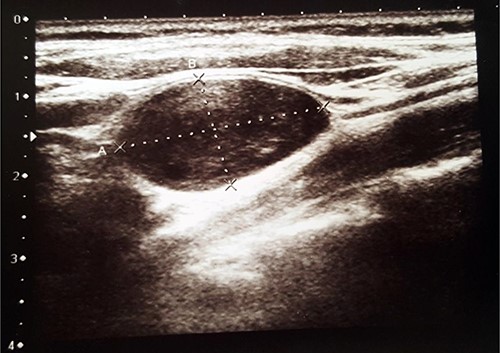

US revealed normal size, with hypoechogenic nodules thyroid gland and a heterogenic 2.6 × 1.4-cm size ovoid shape mass in the left side of the neck (Fig. 1). The tumour was misunderstood to be a lymph node and malignant process was suspected. Fine needle aspiration cytology (FNAC) of the mass was performed, but it was inconclusive. The patient was referred to the Department of Surgery for suspected malignant lymph node excision. During physical examination, her blood pressure was 150/90 mmHg and heart rate was 88 times per min. Her electrocardiography showed sinus rhythm. Blood laboratory findings were within normal limits. Clinical examination revealed firm, non-tender, ~3 × 2-cm size mass in the left side of the neck.

Radiologic imaging plays an important role in diagnosing vagal nerve schwannoma. On US images, it appears as a round or elliptical cross-section with a clear border tumour [1]. Computed tomography (CT) shows vagal nerve schwannoma as a well-covered, well-defined mass [1, 4], which is usually of higher attenuation than muscle on contrast-enhanced images [4].